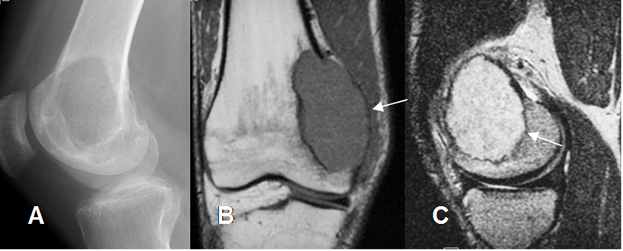

Fig 124 A. Tumor de células gigantes.

A: RM axial en T1, B: RM sagital en T2 y C: RM coronal en STIR. Tumor de células gigantes en la vaina tendinosa flexora del pulgar, manifestado por imagen ovalada y sólida, hipointensa en todas las secuencias.